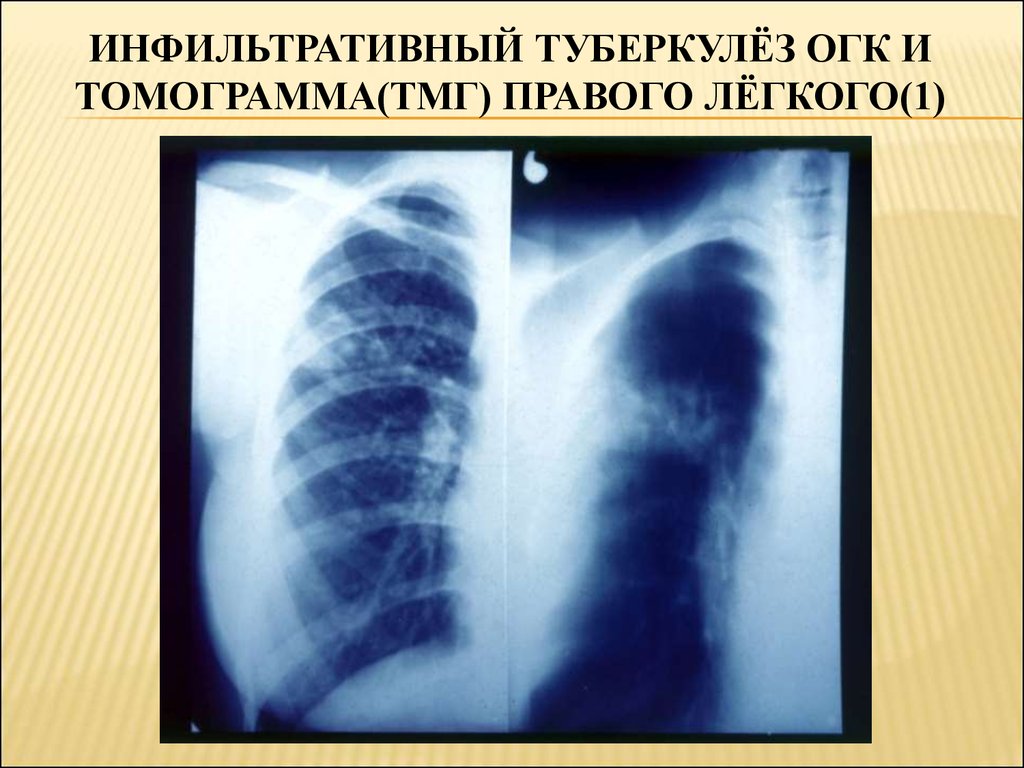

Очаговый и инфильтративный туберкулез презентация - 94 фото